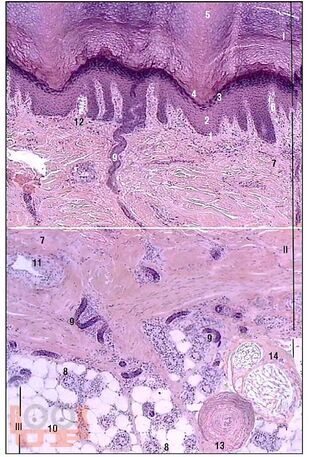

В учебном пособии представлены сведения о кожном покрове и его производных. Также представлены классификации основных поражений кожи и ее придатков, подкожного жирового слоя.